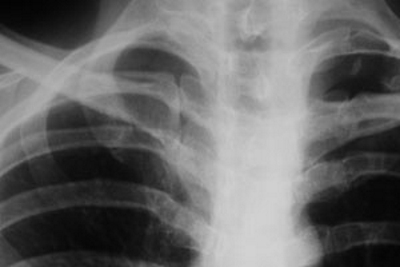

Травма ребра требует внимательного наблюдения врача-травматолога, который должен исключить возможность перелома, пневмоторакса (скопление воздуха в плевральной полости), гидроторакса (наличие жидкости в плевральных полостях) и ушиба легкого.

Для этого проводятся следующие диагностические процедуры:

- рентгенография грудной клетки для определения характера повреждений;